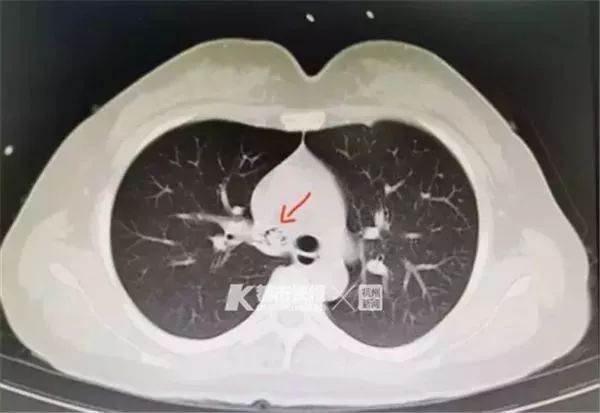

意识到情况不对的她,在老公的陪同下赶往浙江医院三墩院区急诊科就诊。CT检查结果显示,在于女士的右肺中间支气管下端,卡着一个弯曲状的异物,结合于女士的自述,浙江医院呼吸内科杜坚宗副主任医师基本断定“就是那只误吸入肺部的虾”。

随后,陈先生被送至三墩院区急诊,CT显示左主支气管内见一“虾”状异物影,长约3.9cm。后经支气管镜下取异物术,陈先生吞进去的虾顺利被取出。